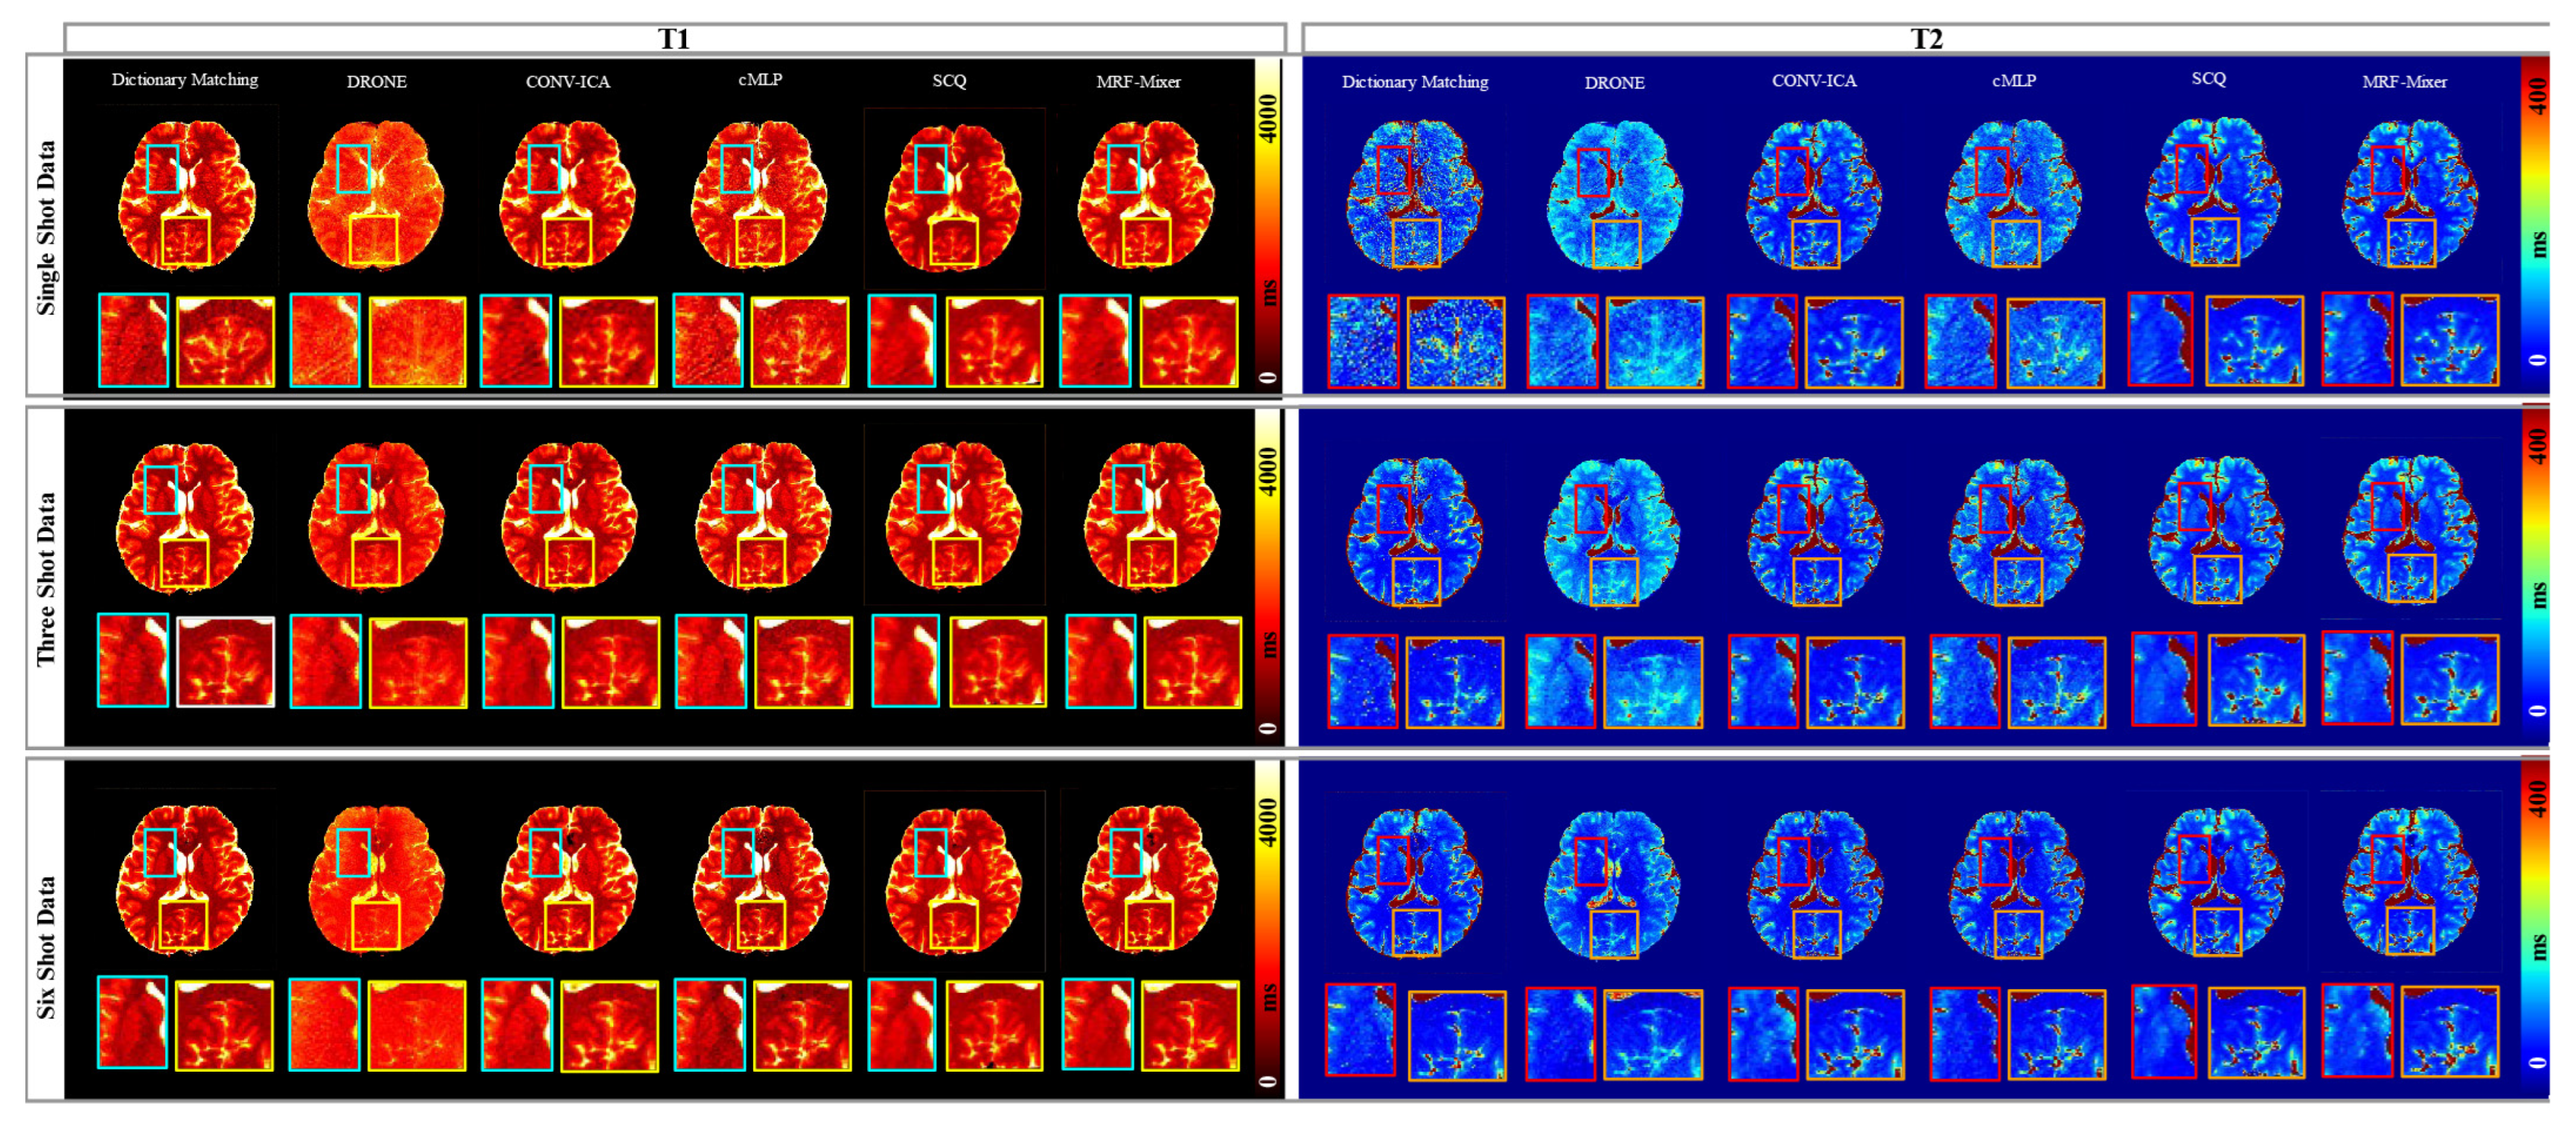

3.2. Simulation Results

3.3. In Vivo Experimental Results